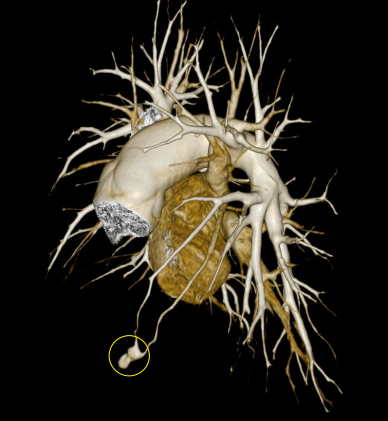

Công nghệ tim mạch Aheart

Phương pháp chỉnh sửa ECG

Hình ảnh lâm sàng